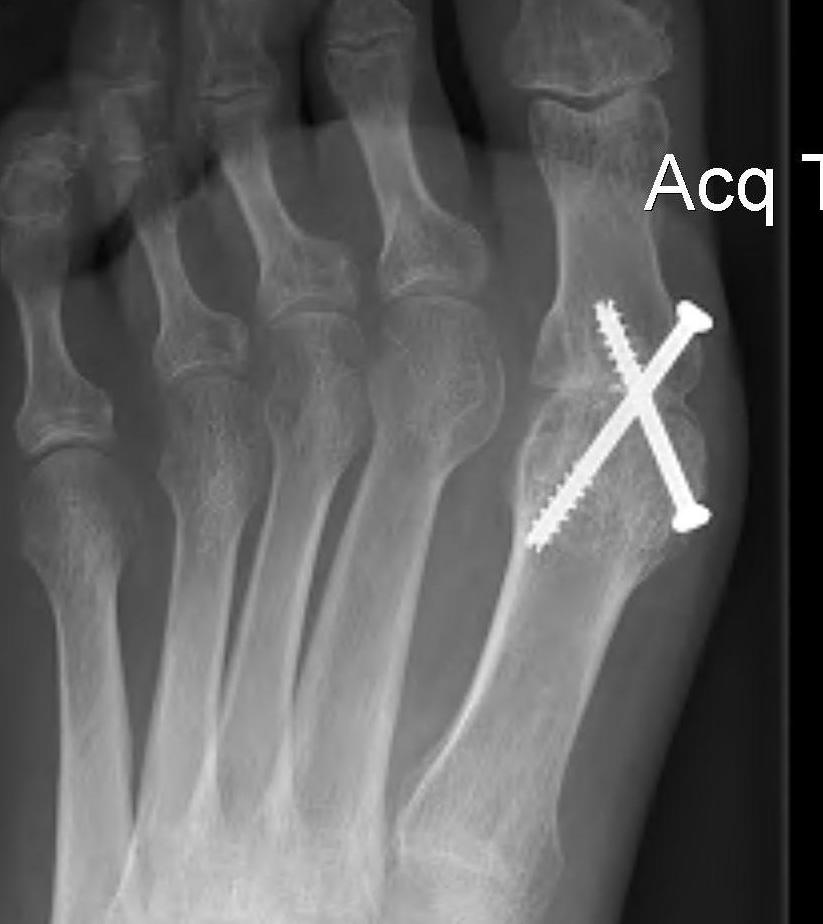

Arthrodesis

Indication

- advanced OA

- young, active patient

Screw fixation

Plate fixation

Screw + plate fixation

Fixation

- screws / plate / screws + plate